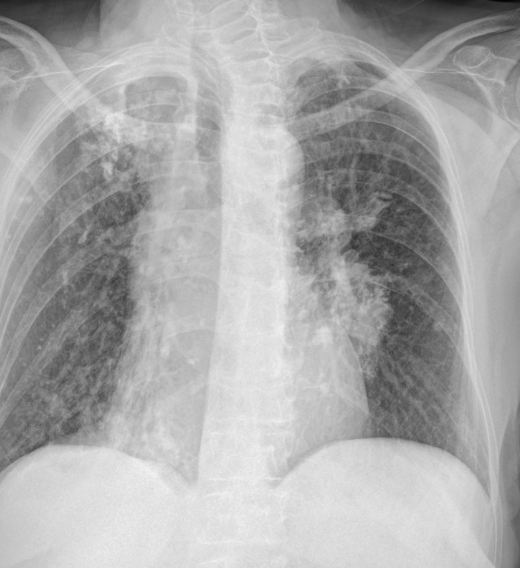

Rx PA de tórax en bipedestación

HALLAZGOS RADIOLÓGICOS

Opacidad heterogénea en vértice pulmonar derecho con engrosamiento pleural apical

Opacidad heterogénea en el vértice pulmonar derecho con derrame pleural

Opacidad difusa mal definida en el vértice pulmonar derecho con engrosamiento pleural apical

Opacidad difusa mal definida en el vértice pulmonar derecho con derrame pleural